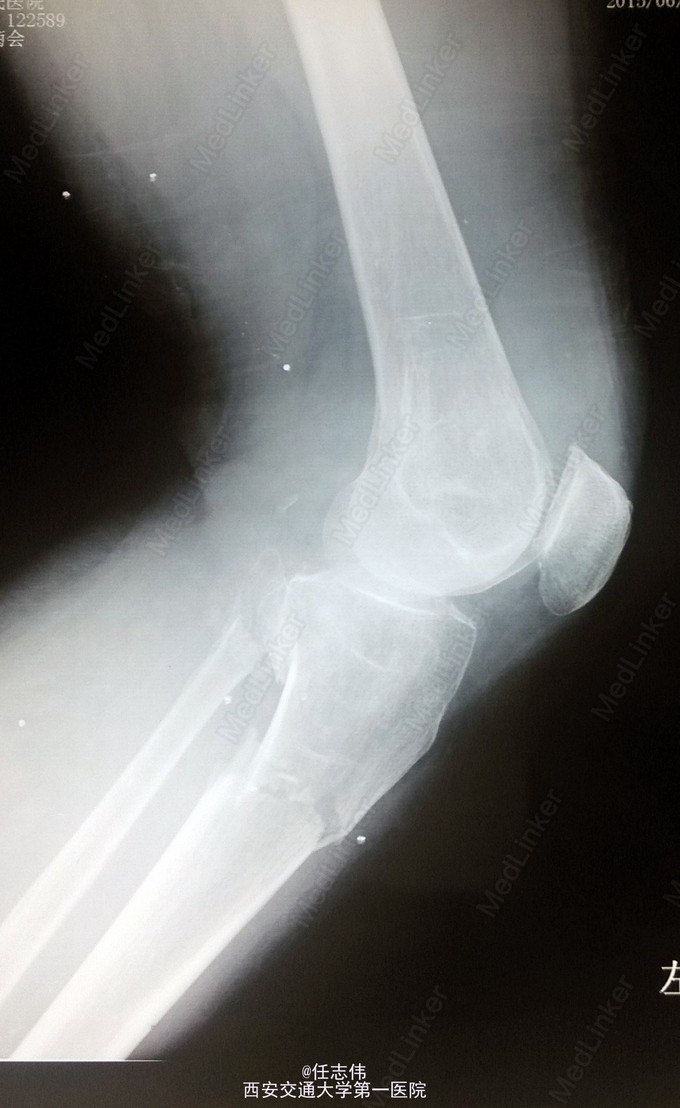

女性,66岁,摔伤致左膝部疼痛活动受限7天 7天前摔伤致左膝部疼痛伴活动受限,在当地医院行跟骨牵引、消肿对症治疗7天,已基本消肿,足部感觉、活动、血供正常。 既往有糖尿病史。

左膝关节周围肿胀,胫骨平台处压痛明显,外侧为著,膝关节活动受限。左足背动脉搏动好,踝及足趾感觉活动正常。

诊断:右胫骨平台骨折 处理:骨折切开复位内固定术。行内外侧入路钢板固定,术中行外侧平台塌陷复位,髂骨植骨内固定。另因考虑有后柱骨折,遂行后外侧切口,支撑钢板固定。术中见患者骨质疏松明显。 术后伤口愈合好,局部仍肿胀明显。